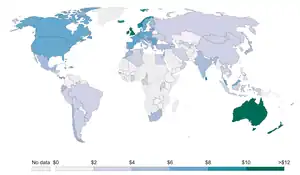

Several countries have taken measures to control the consumption of tobacco (smoking) with usage and sales restrictions as well as warning messages printed on packaging. Additionally, smoke-free laws that ban smoking in public places such as workplaces, theaters, and bars and restaurants have been enacted to reduce exposure to second-hand smoke.[3] Tobacco taxes that increase the price of tobacco products have also been enacted.[3]